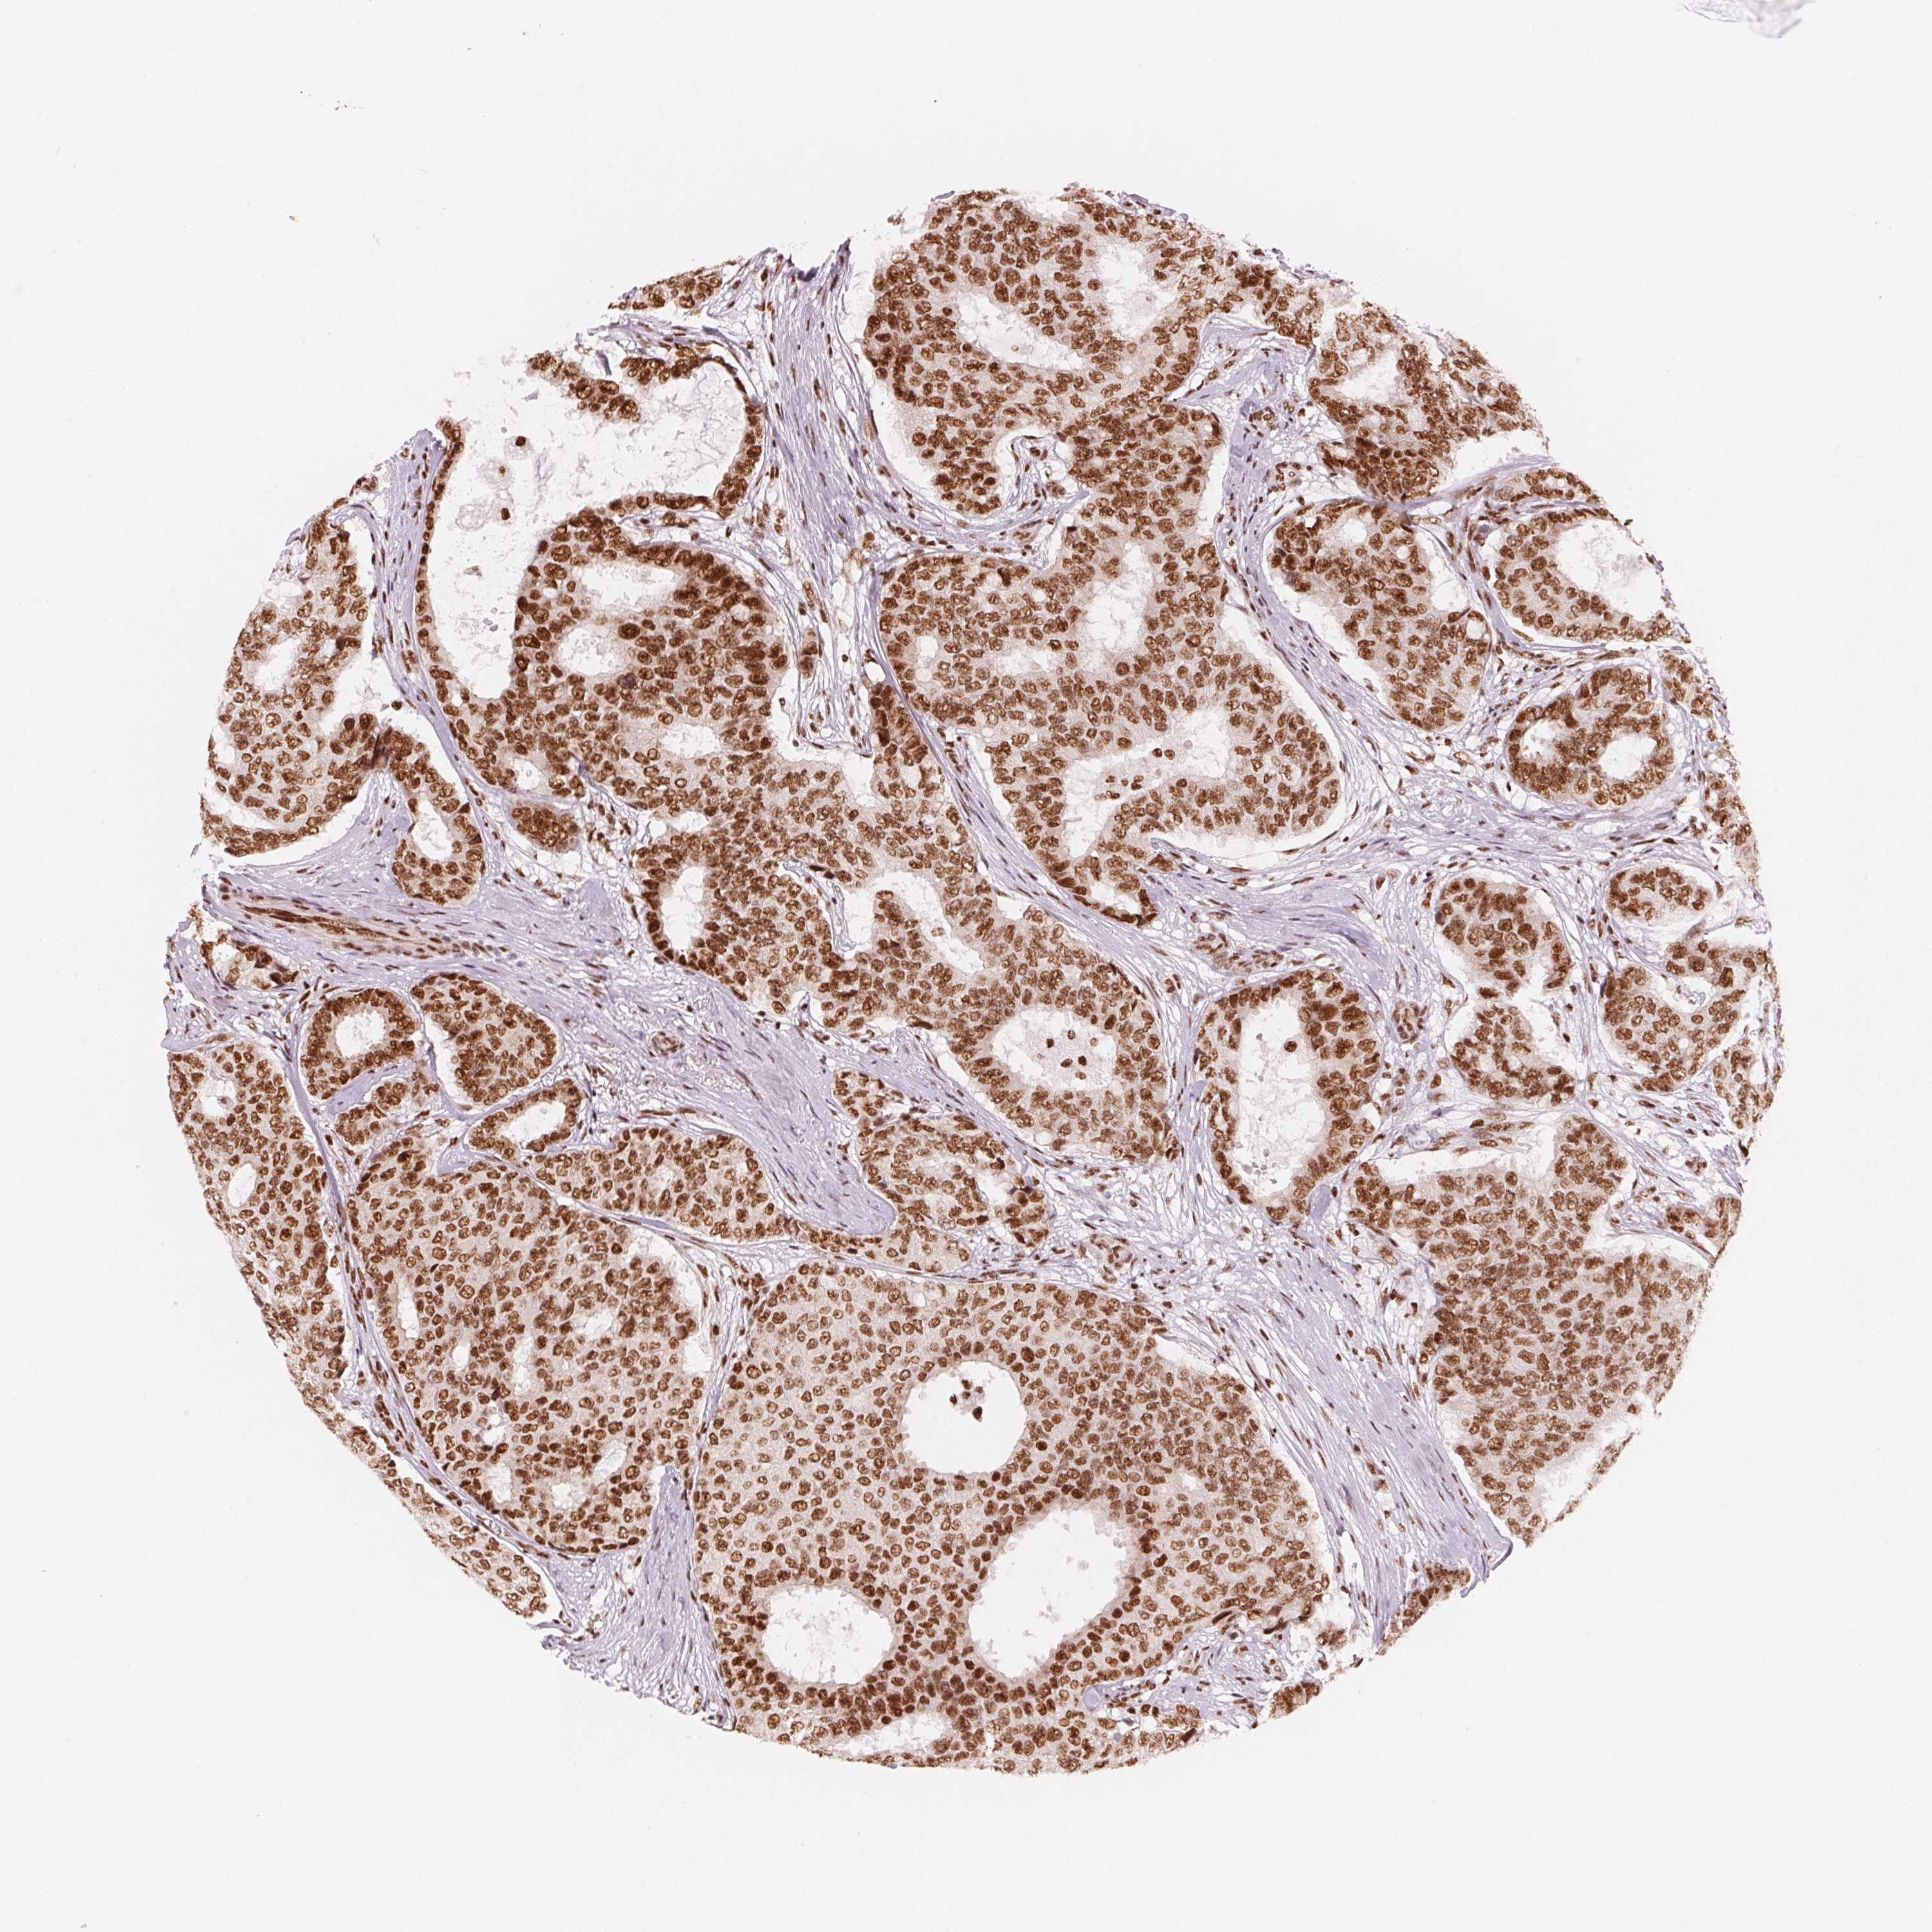

BRCA TCGA BRCA VALIDATION PROTEIN EXPRESSION